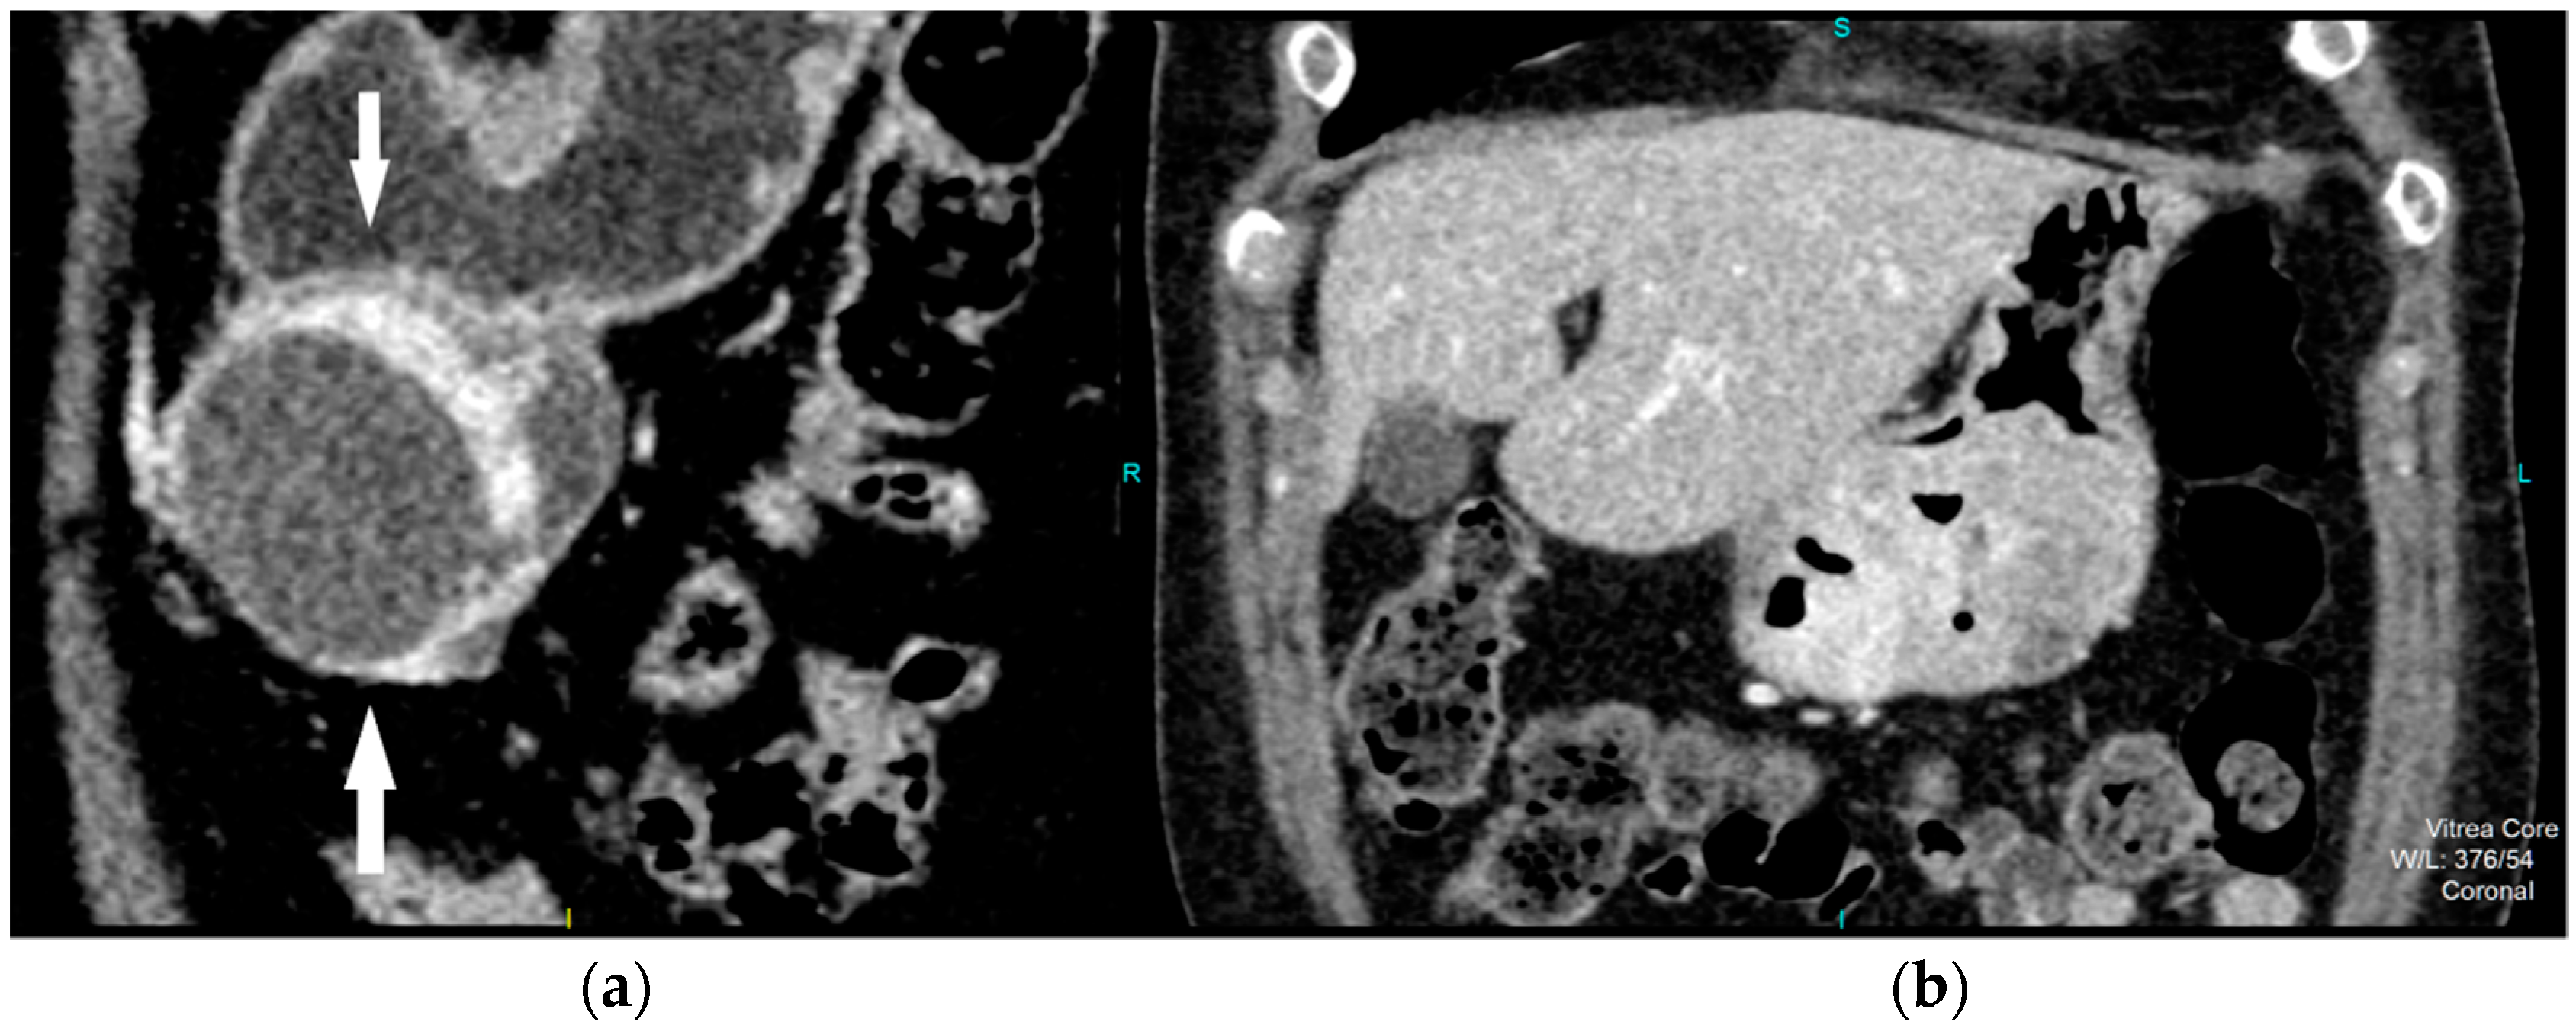

CT imaging features were analyzed as follows: maximal diameter in the axial slice and tumor structure, which was classified into cystic and solid/necrotic. The shape was depicted as regular or irregular. Tumor localization considered the body of the stomach, antrum or pyloric region. Mucosa was observed in two ways: intact/continuous or disrupted. Growth patterns were categorized as exophytic/mixed or endophytic. The degrees of enhancement of the solid part of tumor tissue were divided into weak, moderate or obvious enhancements. The presence of enlarged feeding or draining vessels (EFDV) was also recorded, as was the presence of metastasis in liver and other organs ( Figure 1, Figure 2 and Figure 3).

Figure 2. Contrast enhanced CT, coronal view, shows high risk GIST in a 69-year-old female patient, with a clearly demarcated submucosal lesion in the antrum of the stomach with an exophytic growth pattern and predominantly cystic structure with the strong post-contrast enhancement of solid part of tumor (arrows) (a). CT examination, coronal section, in a 49-year old female patient reveals intraluminal predominantly solid tumor lesion with irregular shape and margins, endophytic growth with the discontinuity of gastric mucosa and obvious post-contrast enhancement in a HR GIST (b).

Figure 3. Contrast enhanced CT exam, coronal view, in a 49-year old female patient shows irregular shape and EFDV (white arrow) of a HR GIST.